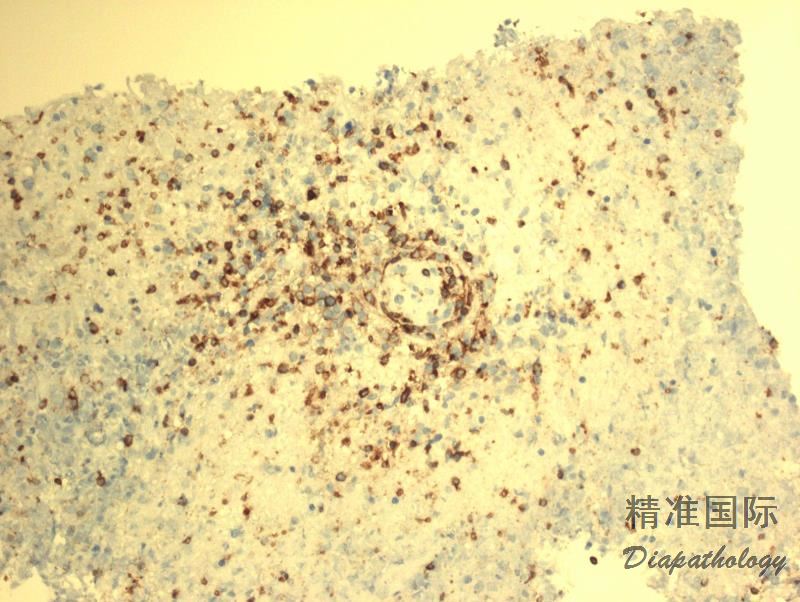

肿瘤细胞表达全 B 细胞抗 CD19. CD20. CD79a、PAX5,CD45+,CD30+/-,CD15-,EBER+;反应性小淋巴细胞表达 T 细胞抗原 CD3. CD5. CD4. CD8(CD4>CD8)。

免疫组织化学染色:

肿瘤细胞表达全 B 细胞抗 CD19. CD20. CD79a、PAX5,CD45+,CD30+/-,CD15-,EBER+;反应性小淋巴细胞表达 T 细胞抗原 CD3. CD5. CD4. CD8(CD4>CD8)